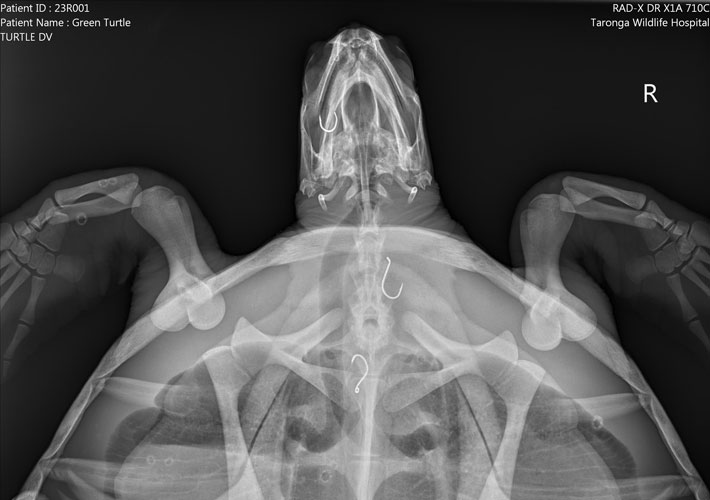

One of the Green Turtles was brought in on 6 January and an x-ray showed it had swallowed five fishing hooks. Since being nursed by the hospital team, only one hook remains, and the team is hopeful that the turtle will make a full recovery. Another Green Turtle was admitted to the hospital in May when it was only a hatchling, and it had a stomach full of plastics. More than six months later, it is on the road to recovery but still needs ongoing care.